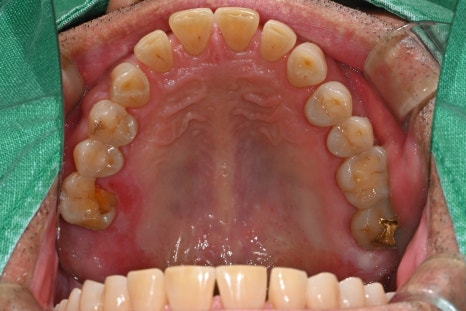

He was a man in his 60s. His upper right molar suddenly broke, and he experienced severe pain while chewing, along with swelling of the surrounding gums.

For patients like this, implant treatment is the most ideal method.

A detailed examination was carried out through panoramic imaging and CT scans.

The examination results showed not a simple cavity or crown fracture, but cracks extending to the root area.